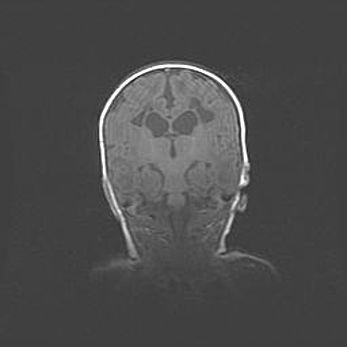

Сообщающаяся гидроцефалия. Кистозная энцефаломаляция головного мозга.

Возраст: 3 месяца 4 дня

Вес: 3100 г

Пол: женский

Окружность головы: 34 см

Срок гестации: 31 неделя

Кистозная энцефаломаляция головного мозга - одна из форм поражения головного мозга в детском возрасте. Характеризуется возникновением множественных и распространённых кист в коре, белом веществе и подкорковых образованиях головного мозга у плодов, новорождённых и детей раннего возраста. Развитие кистозной энцефаломаляции связано с внутриутробной асфиксией и гипотонией, родовой травмой, тромбозом синусов, пороками развития сосудов, инфекциями, сепсисом и другими причинами. Наиболее значимые инфекционные агенты: вирусы простого герпеса, цитомегалии, краснухи, токсоплазмы, энтеробактерии, золотистый стафилококк и другие.